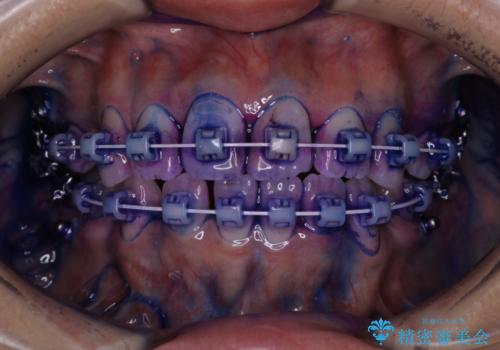

毎日しっかりと磨いているようでも、装置の周りや歯と歯の間・歯と歯茎の間に磨き残しが残ってしまいます。そのため磨き残しをチェックする『染め出し剤』を使用すると明確に磨き残しを見ることができます。

染め出されている部分の磨き残しは、毎日の習慣として歯ブラシをしていてもいつも磨けてない部分です。